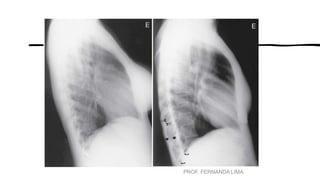

• •Identificar e contar os pares

de costelas.

• (O 1º e 2º pares são os mais

difíceis de localizar.)

• Observar o grau de

deslocamento

do diafragma para baixo

através da contagem dos

pares de costelas

projetadas acima

das cúpulas do

diafragma.

• Uma regra geral para a

média dos adultos

é “mostrar” um mínimo

de dez costelas no tórax

em PA ideal.